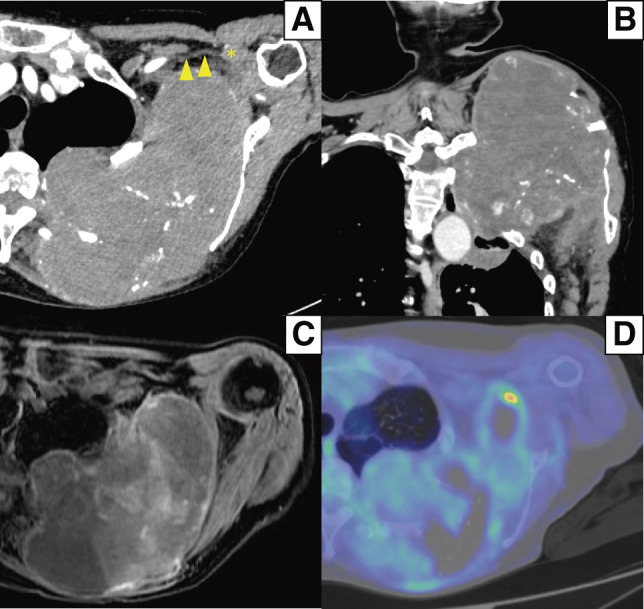

Chronic expanding hematoma (CEH) is defined as a hematoma that gradually expands over months to years. An 82-year-old female underwent proton radiotherapy for left upper lobe lung cancer 10 years previously. Two years after the therapy, a hematoma developed from the left 3rd to 5th dorsal rib fractures and gradually expanded, causing contraction of the left shoulder. Transcatheter arterial embolization was performed; however, the hematoma continued to expand with thrombocytopenia, and the platelet was decreased to 4.2 × 104/μL. Computed tomography showed a 17.2 × 14.0 × 10.0 cm mass between the left scapula and left dorsal ribs. The CEH of the thorax was completely excised with combined resection of the 3rd to 5th ribs, while the brachial plexus was preserved. Postoperatively, the platelet completely recovered and she could raise her left arm. A complete excision with surrounding organs preserved is the strategy used in the treatment of CEH of the thorax.